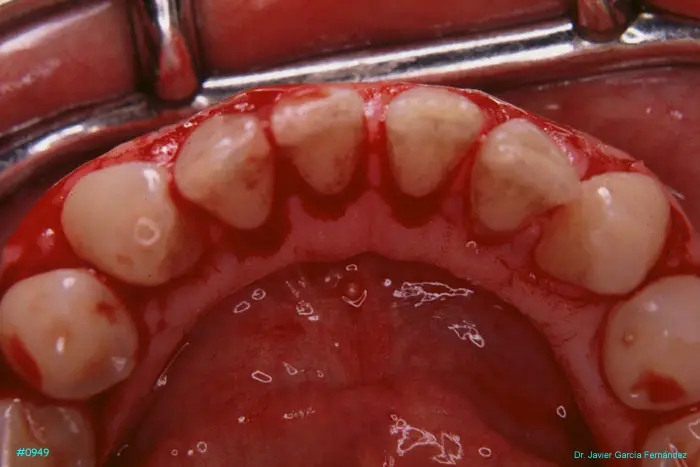

Atlas of Surgical Techniques in Periodontics. Chapter III. Atlas de Técnicas Quirúrgicas en Periodoncia